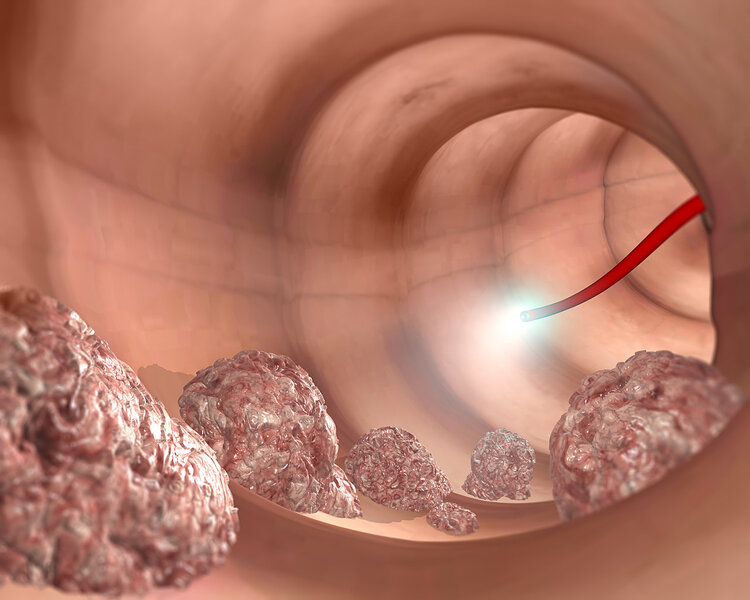

4、直肠癌:肠镜千万要记住

肠镜是筛查出直肠癌的最常用,也是最有效的检查。通过结肠镜直视下,能够清楚地看到黏膜表面是否有溃疡充血的情况,并对可疑病灶做病理活检。对于40岁以上有家族史的人群,建议定期地做直肠肠镜检查。